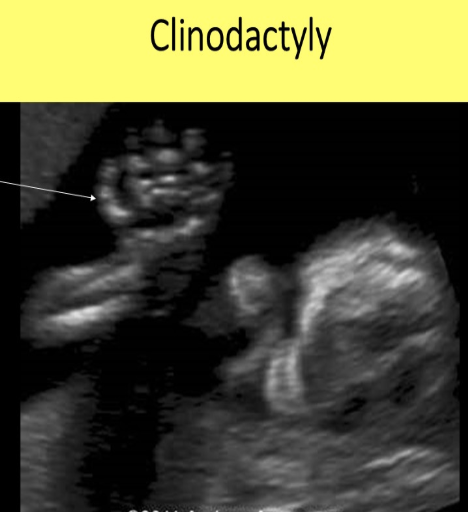

pt has 20w gestation. she has hx of prior pregnancy w/clinodactyly [curving of pinky]. what is the best way to evaluate

.

a) measure the humerus length

b) measure the length of the middle phalanx on the 5th digit

c) assess hands/feet for proper digit formation

d) evaluate the cranial anatomy for cerebral clefts